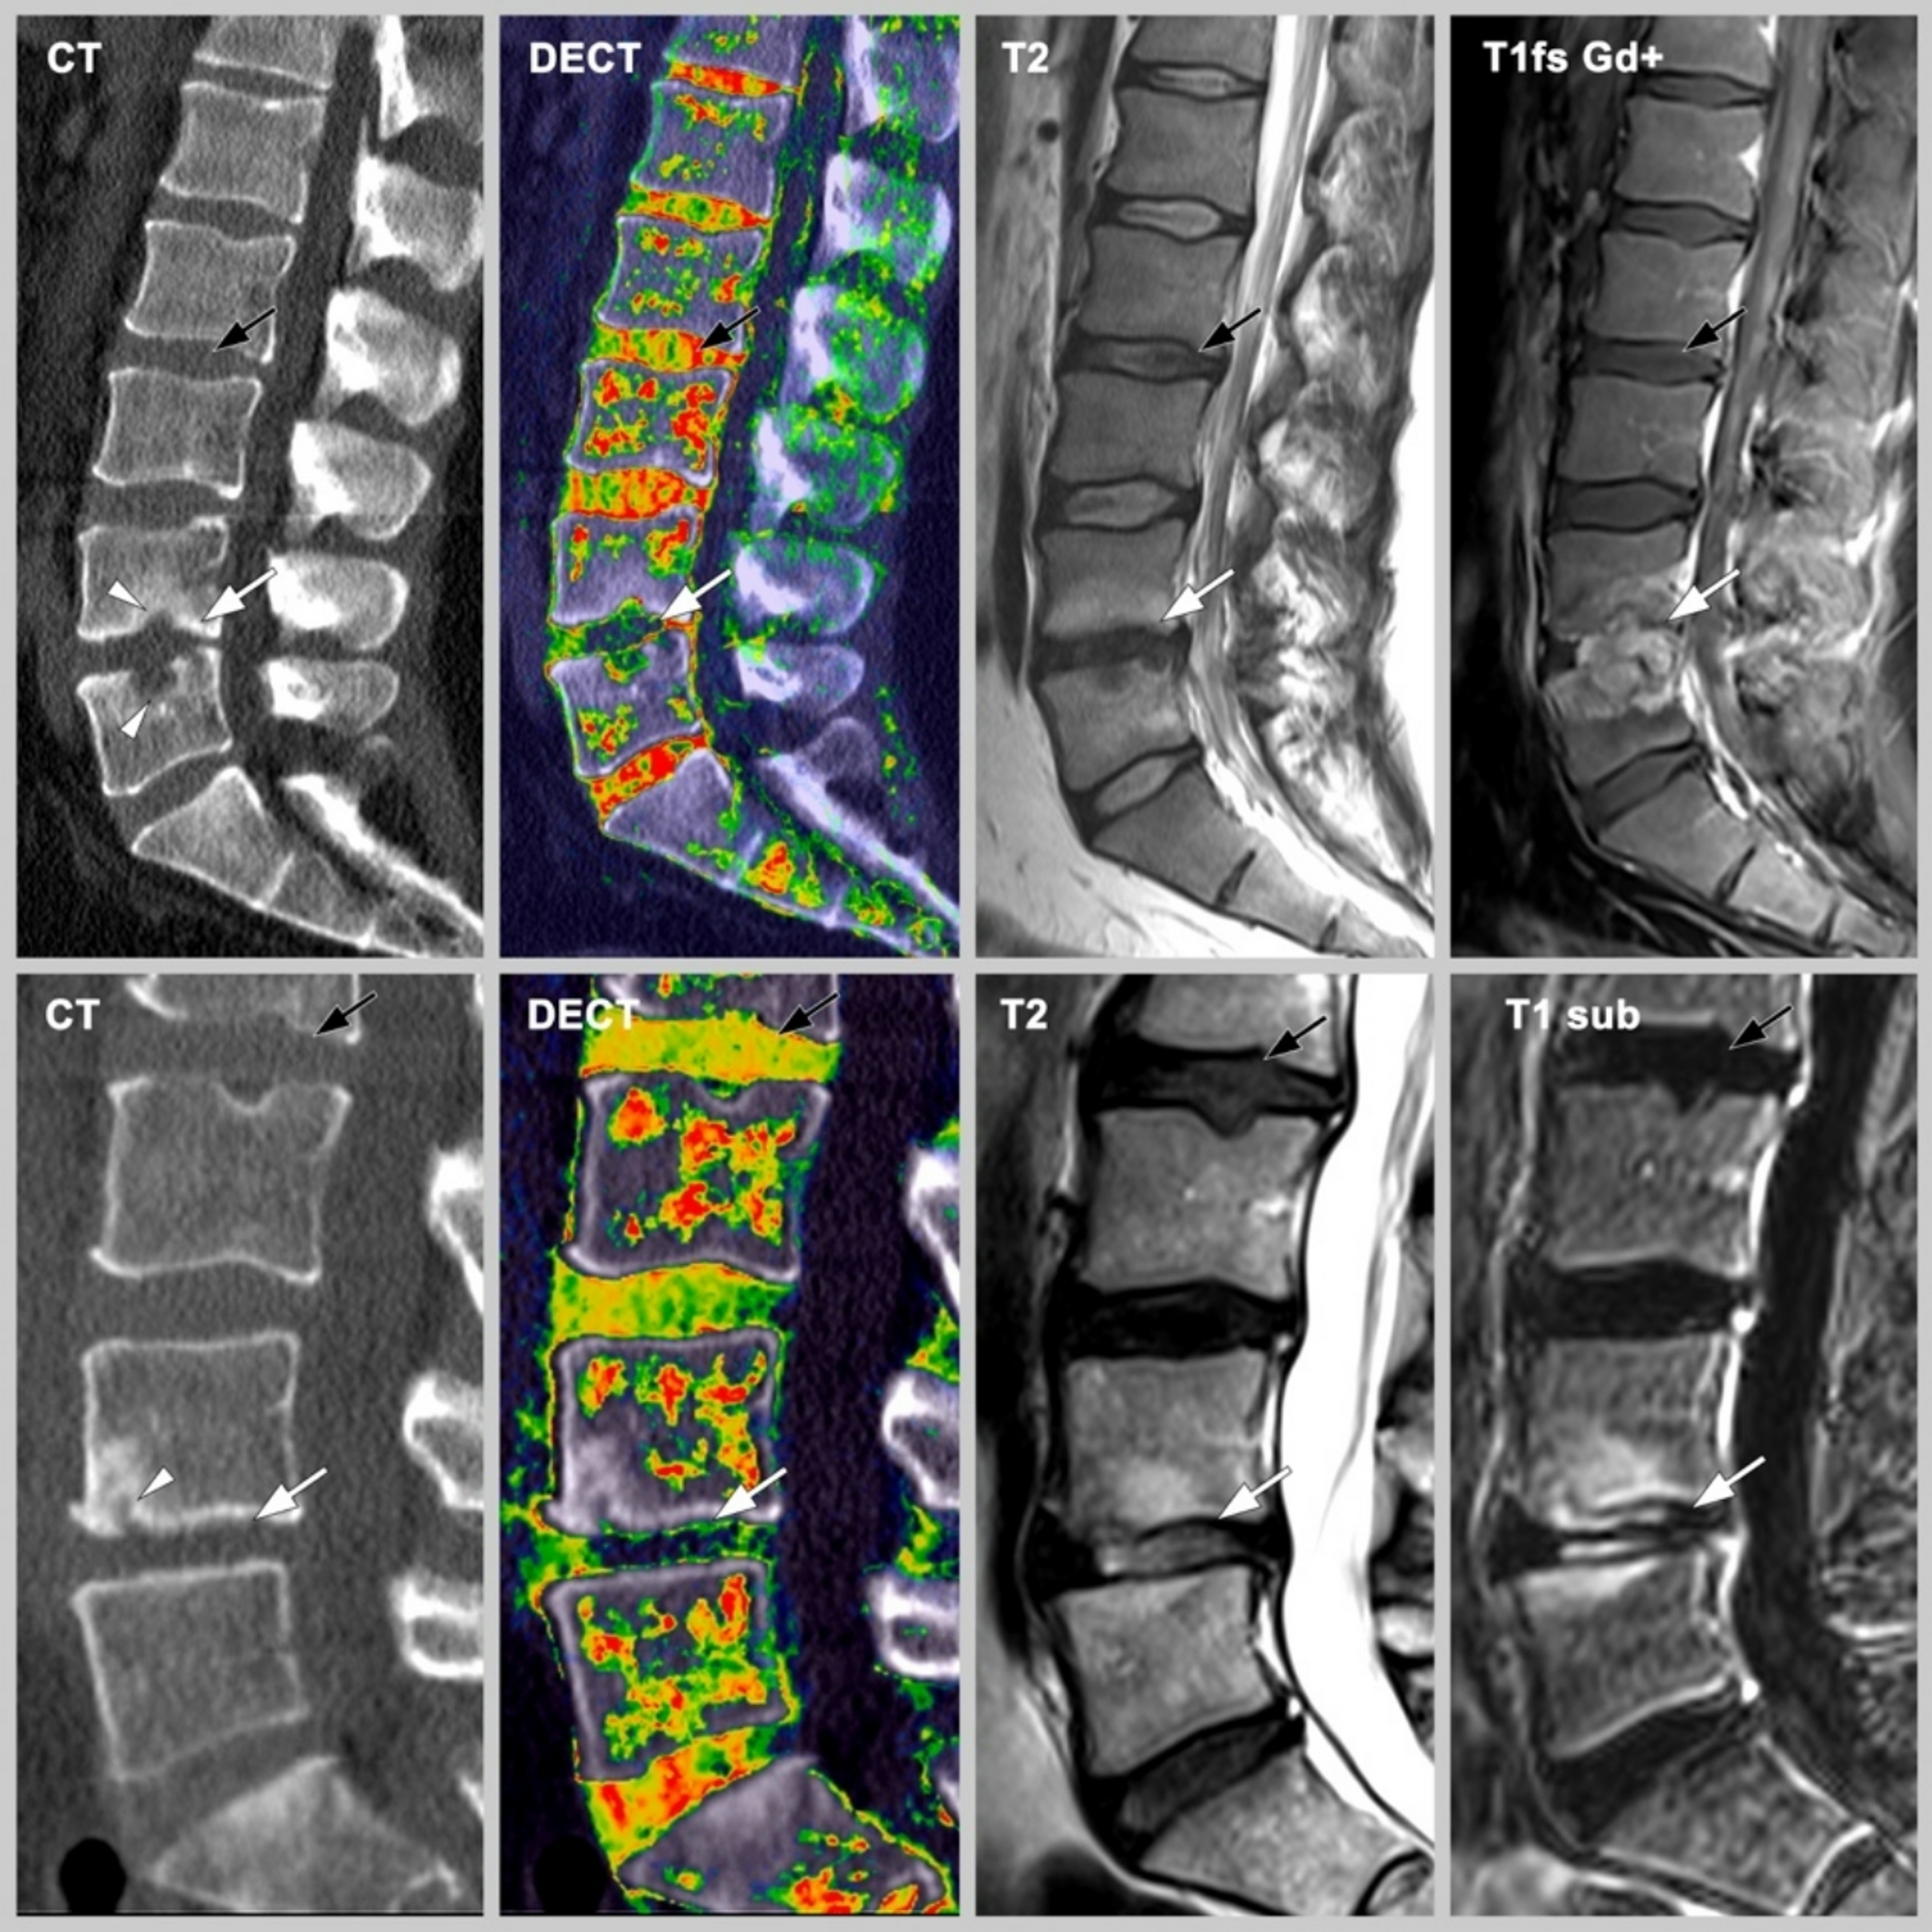

Fig. 3

From: Diagnostic accuracy of dual energy computed tomography for suspected pyogenic spondylodiscitis

Images obtained in two patients with different spinal abnormalities. Images are sagittal reformations at 3 mm slice thickness and include conventional CT images, DECT cMaps, and T2-weighted MR images, and T1-weighted MR images T1fs Gd + and T1 sub. Patient 1 (upper row): Spondylodiscitis of the L4/5 disc (white arrow). Patient 2 (lower row): Disc degeneration (white arrow) with erosion (white arrowhead) at the L4/5 level. The black arrows point to normal discs for comparison, respectively.CT: Computed tomography; cMaps: Collagen-/chondroitin-sensitive map; DECT: Dual-energy computed tomography; MRI: Magnetic resonance imaging.